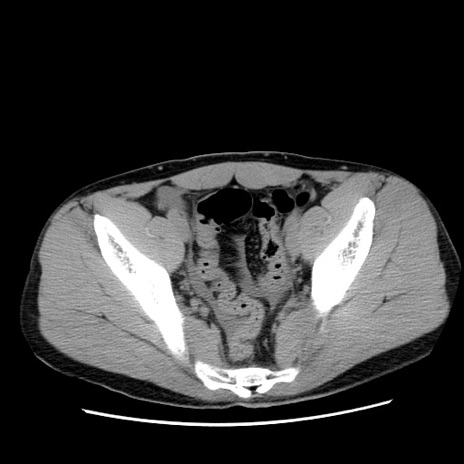

症例36(横断像)

【症例】20歳代 男性

【主訴】心窩部痛

【現病歴】今朝より上腹部痛あり。一旦軽快していたが再度出現したため救急要請。昨日夕に白身の魚を含む刺身を食べた。

【身体所見】BP 136/89mmHg、HR 74/min、BT 37.0℃、腹部:膨満、軟、心窩部に圧痛あり。反跳痛なし、筋性防御なし、腸雑音やや亢進あり。

【データ】WBC 17700、CRP 0.48